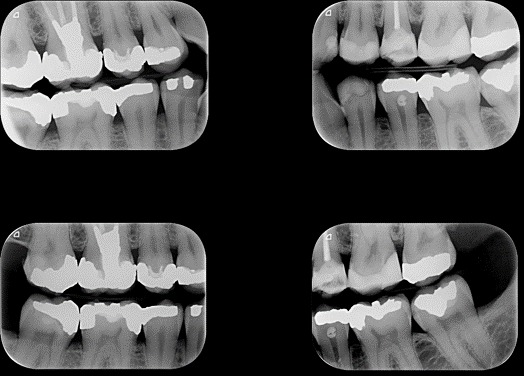

این نوع رادیوگرافی تماسهای دندانی و همچنین استخوان بین دندانها در ناحیه نزدیک به تاج را به ما نشان میدهد و تصویر بسیار مناسبی را جهت بررسی پوسیدگی بین دندانی و همچنین بیماریهای لثه در مراحل اولیه آن را برای ما فراهم می نماید. در این روش بیماربا گاز گرفتن بر روی بالچه های مقوایی و یا پلاستیکی رسپتور را در دهان خود نگاه میدارد و اصطلاح bite wing از همین روش تهیه رادیوگرافی اقتباس شده است. بیشترین مورد استفاده از این روش در دندانهای خلفی است و جهت بررسی کامل دندانهای خلفی حداقل به دو رادیوگرافی در هر طرف نیاز داریم که یکی دندانهای آسیایی بزرگ و دیگری دندانهای آسیایی کوچک را به ما نشان می دهد.

تصویر زیر سری کامل رادیوگرافی خلفی بایت وینگ را نشان میدهد.